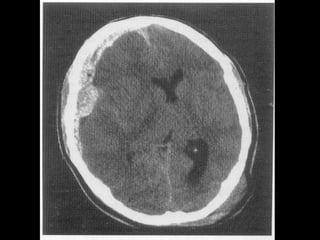

HEMORAGIILE SUBARAHNOIDIENEHEMORAGIILE SUBARAHNOIDIENE

 Se evidenţiază prin examen CT >> sânge în

spaţiul subarahnoidian, de obicei difuz peste

ţesutul cerebral.

 Dacă există şi o hemoragie intraventriculară

majoră >> prognostic rezervat

 Dacă extinderea este limitată, posibil să nu

necesite tratament specific şi prognosticul

este bun.